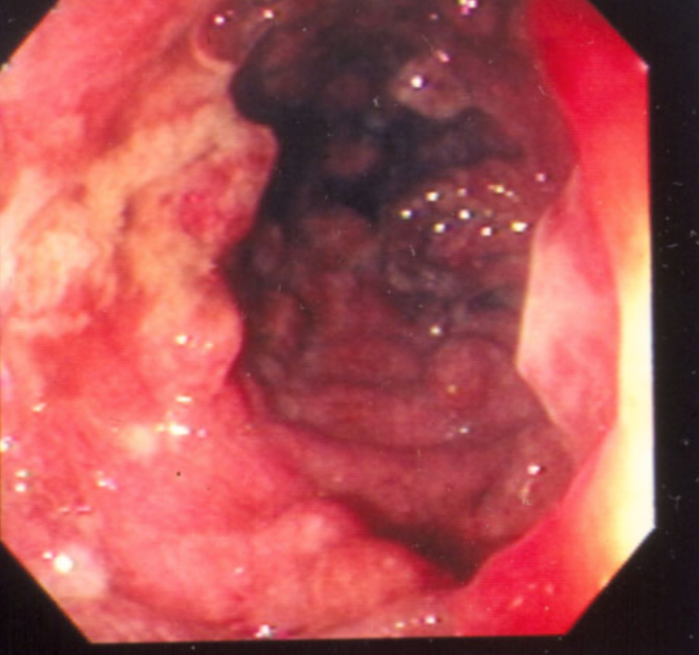

Crohn’s: nodulatiry, ulceration, exudate, luminal narrowing